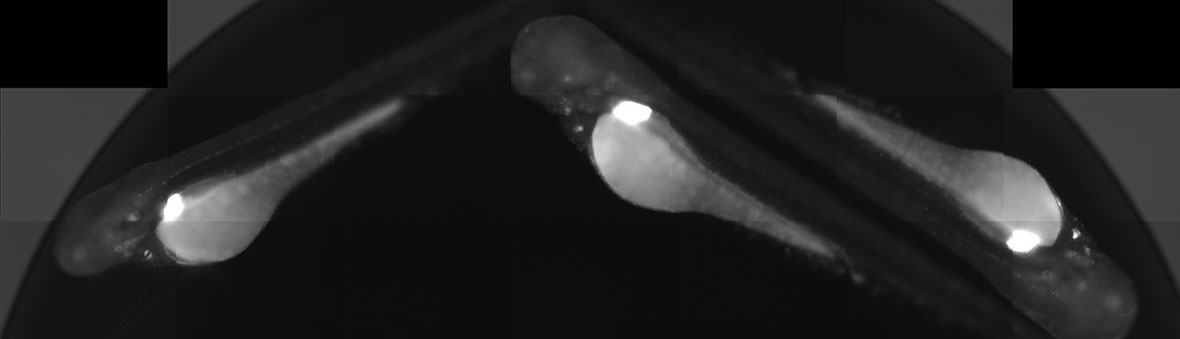

Estradiol (3 nM) activates receptors in the liver (arrow head) and in the heart valves (arrows), whereas genistein (18.5 nM) preferentially activates receptors in the heart valves. Scale bars = 500 μm

We have used transgenic zebrafish that report estrogen receptor activity and identified compounds that preferentially activate receptors in the heart compared to the liver. We are currently expanding this approach to identify selective glucocorticoid receptor modulators that are more potent in certain cell types, such as T-cells, compared to other cell types. The compounds we identify could revolutionize our knowledge of nuclear receptor structure-activity relationships, be used as tools for basic research and serve as the basis to design small molecules for therapeutic use.